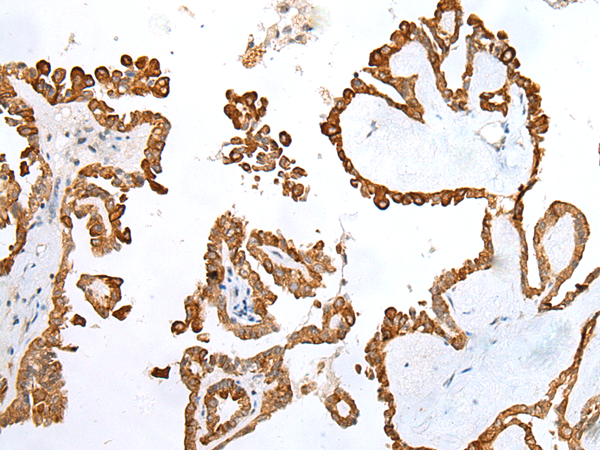

IHC positive control: |

Human thyroid cancer |